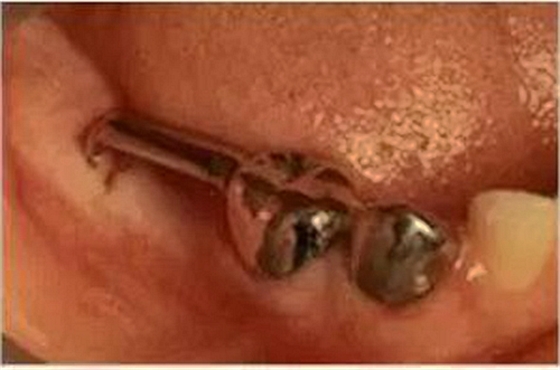

④遠中導板式間隙保持器

乳牙缺失致恒牙“亂長”,這個“間隙保持器”可預防

這種間隙保持器是將導板插入牙齦中,主要用于孩子的六齡牙(最先長出的第一顆恒磨牙)還沒有萌出,但是這個牙前面的乳牙缺失的情況。

因為最后方的牙齒缺失,沒有可以用來固定帶環(huán)絲圈的牙齒,因此需要一個金屬導板插入到牙齦中,防止間隙關(guān)閉。

這種保持器需要經(jīng)常檢查并作出調(diào)整,防止阻擋下方恒牙的萌出。為了減少這種裝置的使用,牙醫(yī)經(jīng)常會盡可能保留乳牙,直到牙齦下方的恒牙已經(jīng)發(fā)育到可以萌出。